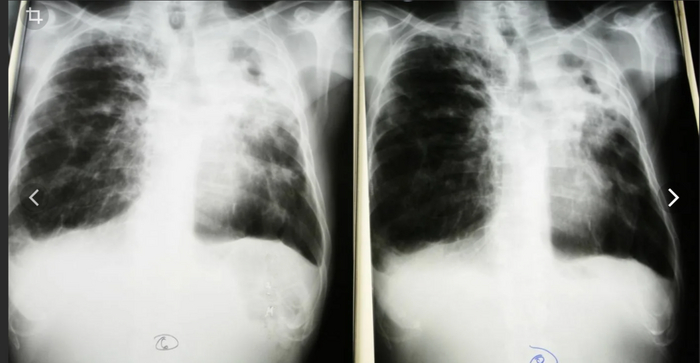

Диагноз, который мне назвал брат - милиарный туберкулез обоих легких, открытая форма. Струхнули все. 7,5 месяцев жить в тесном вагончике с туберкулезником, это вам не в тапки гадить. И все прошли медосмотр в одной частной клинике медосмотров.

Начальство по приказу СЭС всю бригаду снимает, и отправляют домой на дообследование. Вагончик говорят обработали (брат рассказывал) Следом за моими братьями прилетает письмо для фтизиатрической службы о проведении эпидемиологического расследования, проведения дезинфекции домов и постановки на учет всех членов семьи. Мы проверили всех: дядю, тетю, жен братьев, всех детей. Слава богу дети просто попали в категорию контактных... Была конечно пара сомнительных случаев, лично возила на КТ и заставляла сдавать мокроту на анализ 3 раза, но все обошлось. А вот у тех кто жил в вагончике еще у двоих из 8, открытая форма туберкулеза. Сразу положили их на стационарное лечение на год в противотуберкулезный диспансер, потом перевели на амбулаторное долечивание на 3 года. Соответственно ни о какой работе на Севере в этот период речь не идет. А у каждого семья, по трое малолетних детей и кредиты. Скандалы в семье. Постановка на учет у фтизиатра. Сэкономили на медосмотре называется. Мы конечно узнали от кого и как он заразился. Но это уже другая история.